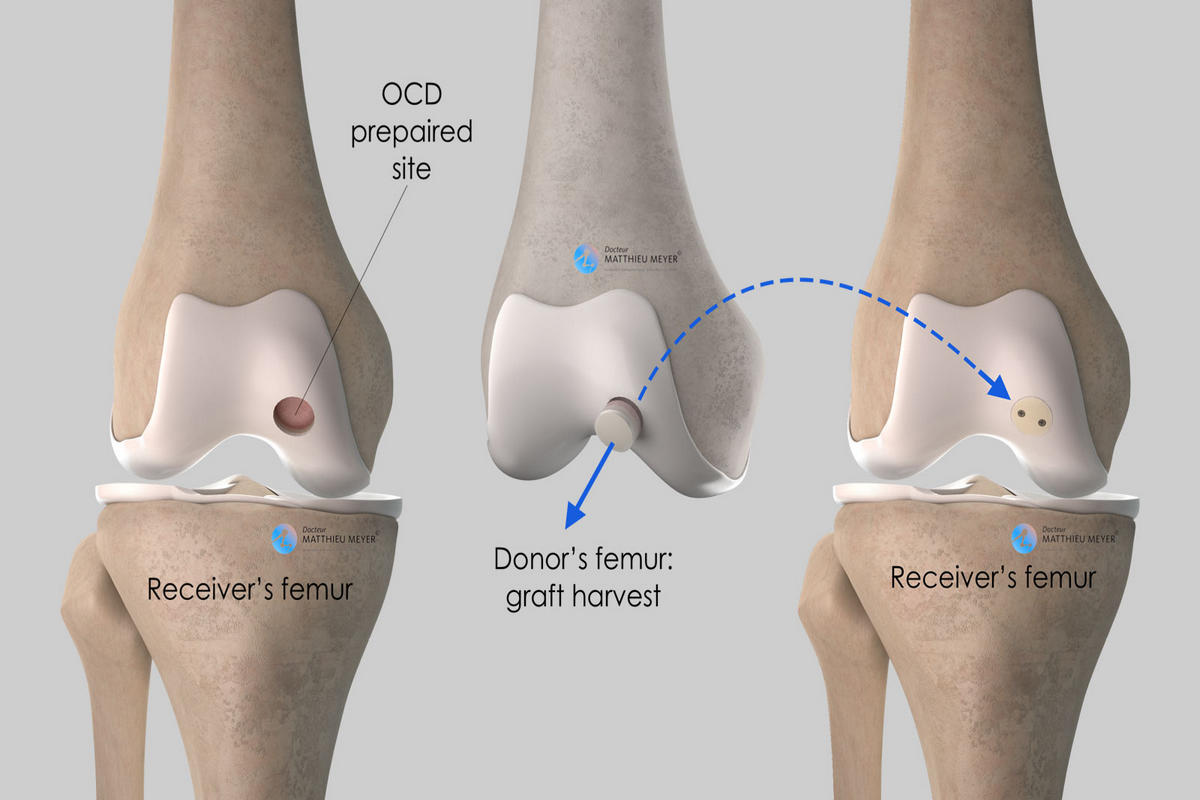

Σε εκτεταμένες ή συμπτωματικές βλάβες ενδείκνυται χειρουργική αντιμετώπιση. Οι σύγχρονες τεχνικές περιλαμβάνουν αρθροσκοπικό καθαρισμό και λείανση της βλάβης, μικροκατάγματα που διεγείρουν τον σχηματισμό ινοχόνδρου, αυτόλογη μεταμόσχευση χονδροκυττάρων και μεταμοσχεύσεις οστεοχόνδρινων κυλίνδρων. Σε περιπτώσεις εκτεταμένης φθοράς μπορεί να εξεταστεί και η λύση της μερικής ή ολικής αρθροπλαστικής γόνατος.